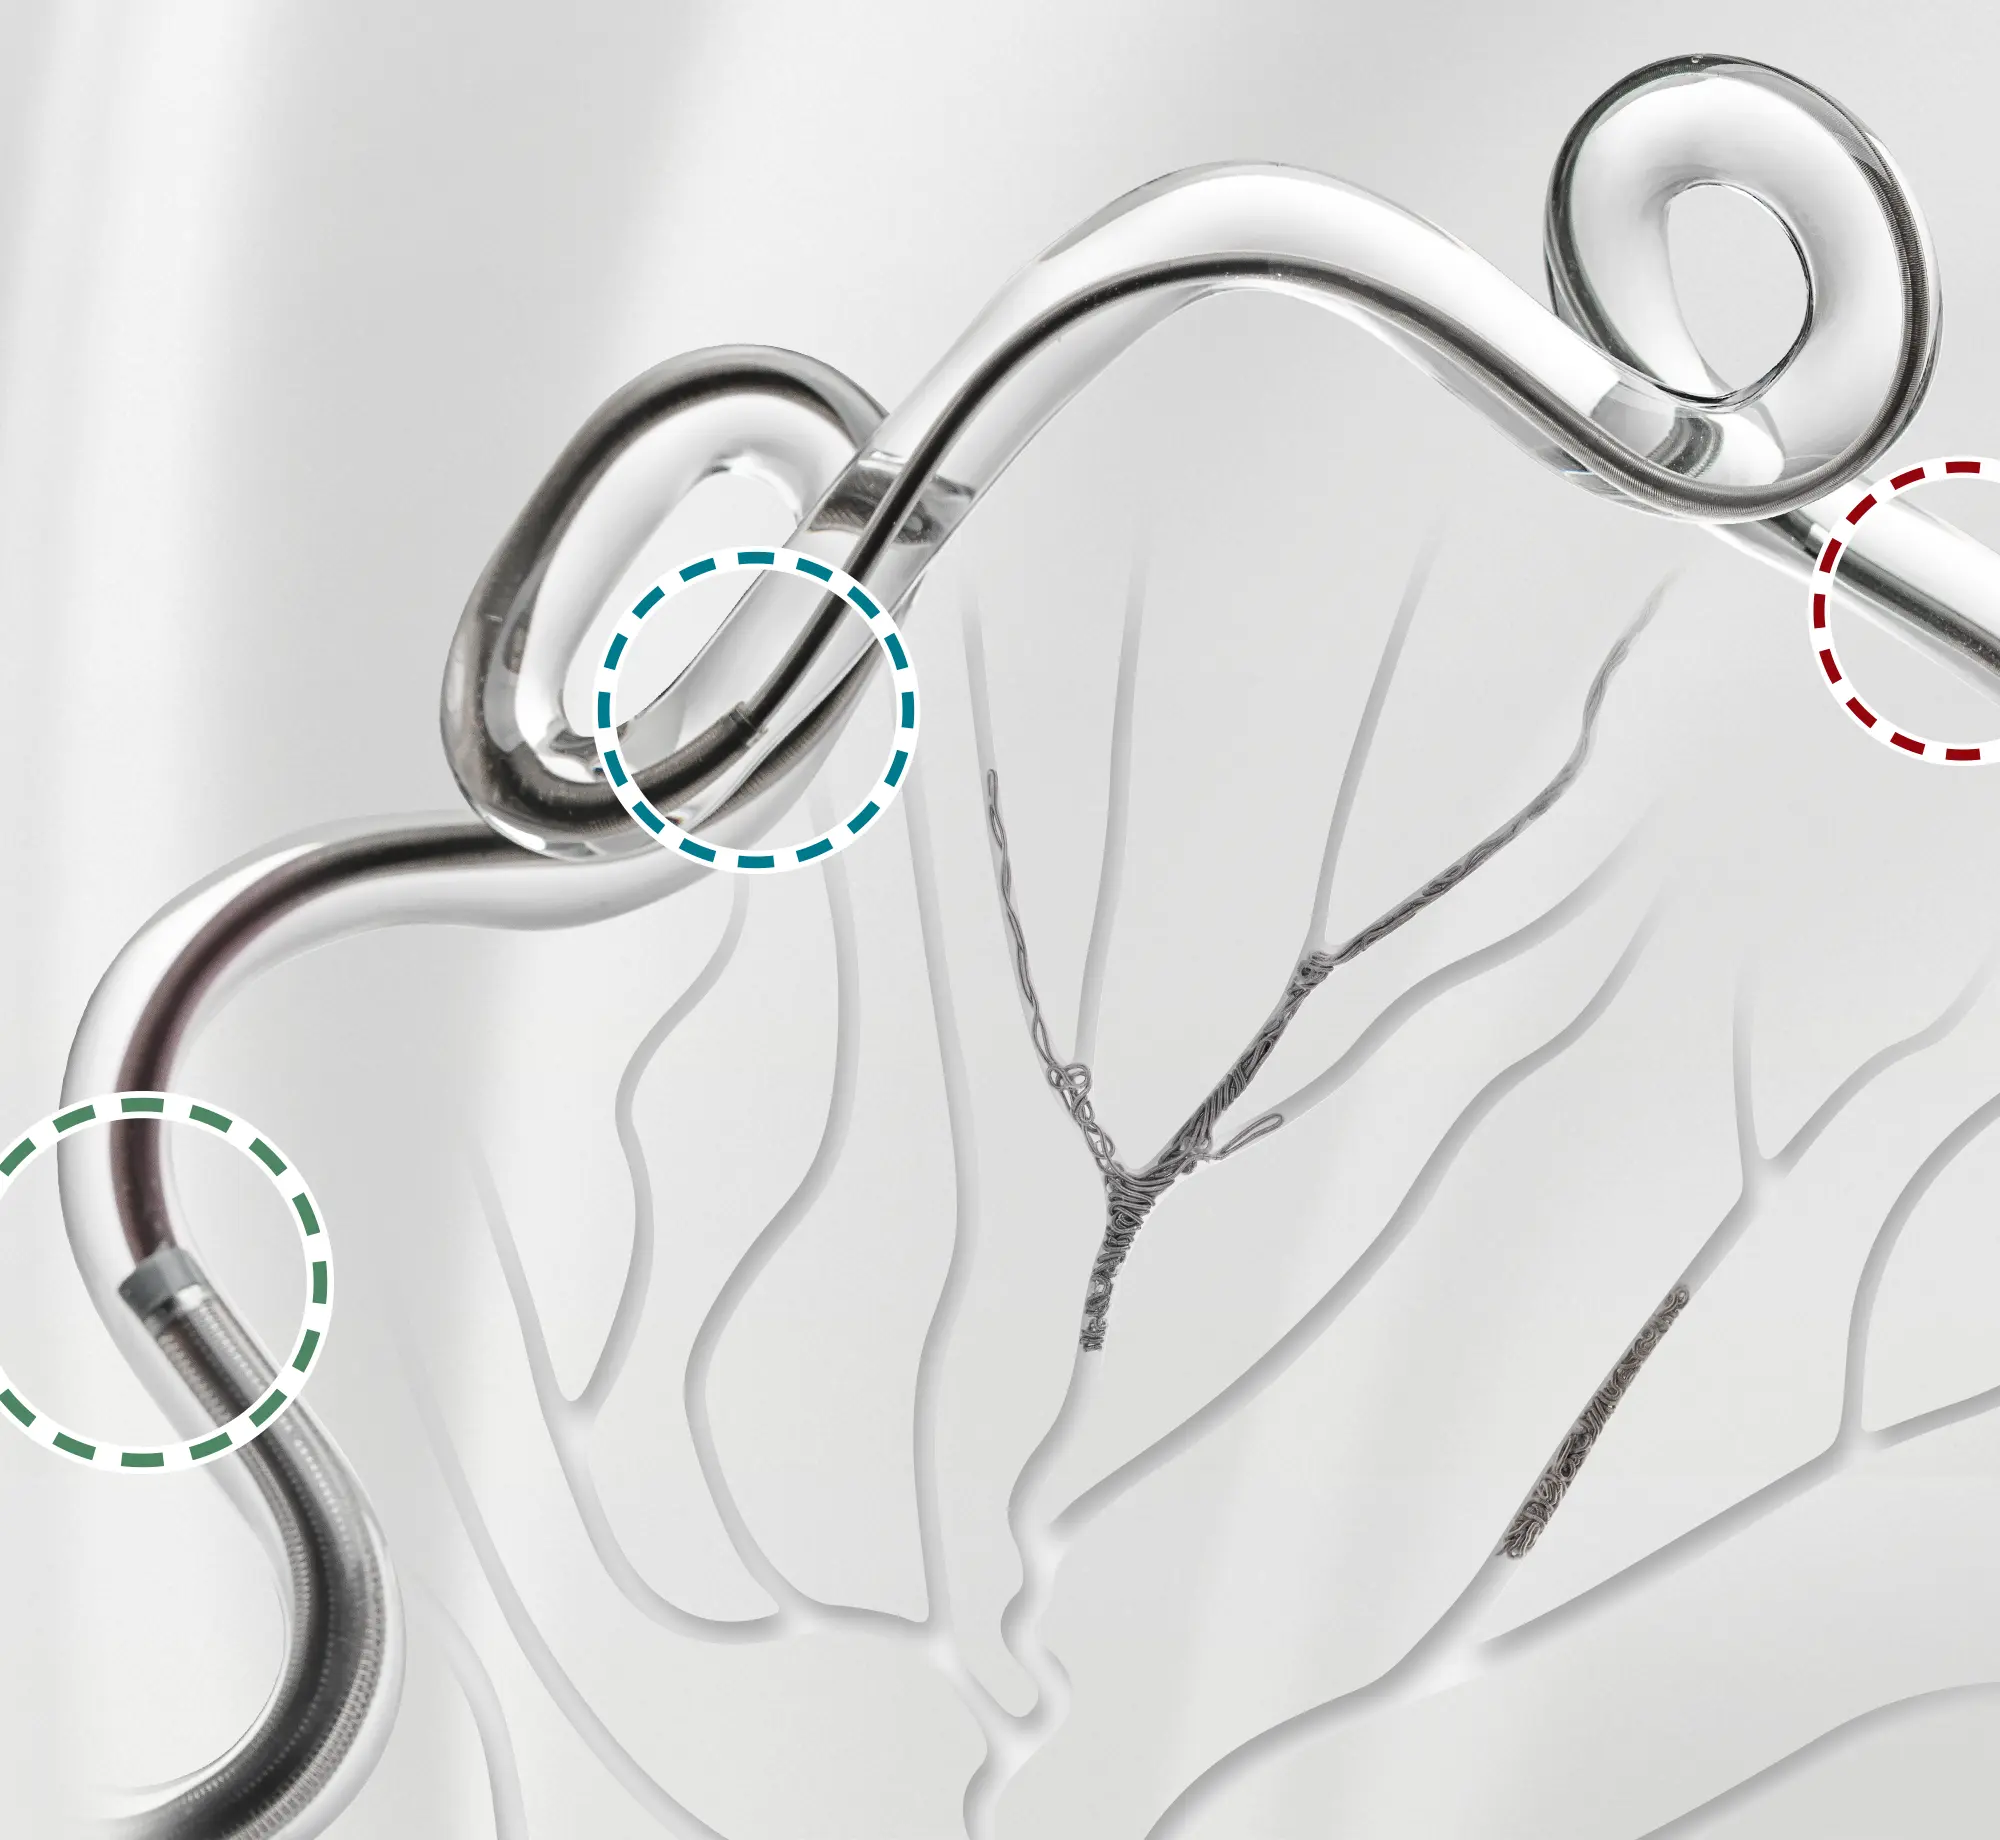

Access. Deliver. Pack.

Designed to Access, Deliver, Pack with confidence in the most challenging cases. Penumbra’s integrated portfolio supports every stage of neurovascular intervention.

Access Catheters & embolization coils being deployed in a glass vessel

• bmx81 access catheter shown close up on a green square background with text that reads "Access"

BENCHMARK BMX Family

• 6, 7, 8 F catheters up to .096″ ID

• Designed to provide access support

• Designed to provide arch support

• Midway Intermediate access catheter shown close up on a blue square background with text that reads "Deliver"

MIDWAY

• Designed for the introduction of interventional devices into the vasculature

• Designed with REDglide™ Coating in tortuous vasculature

• access25 delivery catheter shown close up on a red square background with text that reads "Deliver"

ACCESS25

• Designed for Penumbra’s

.020″ coils

• 90 cm of REDglide Coating: is designed to facilitate smooth trackability

• Designed to resist back-out

• Embolization Coils in a glass model on a red and purple square background with text that reads "pack"

SwiftPAC

• Soft, space-seeking like liquid metal coil

• Designed to conform to the target vessel for dense packing

• Broad lengths ranging from

3-60 cm

• embolization coils forming a spherical shape in a glass aneurysm model on a grey background with the words that read "pack"

PC400

• Designed to support higher packing densities using fewer coils

• .020″ volume advantage over

10-System coils

• Sizes range from

2–32 mm in diameter and

1–60 cm in length